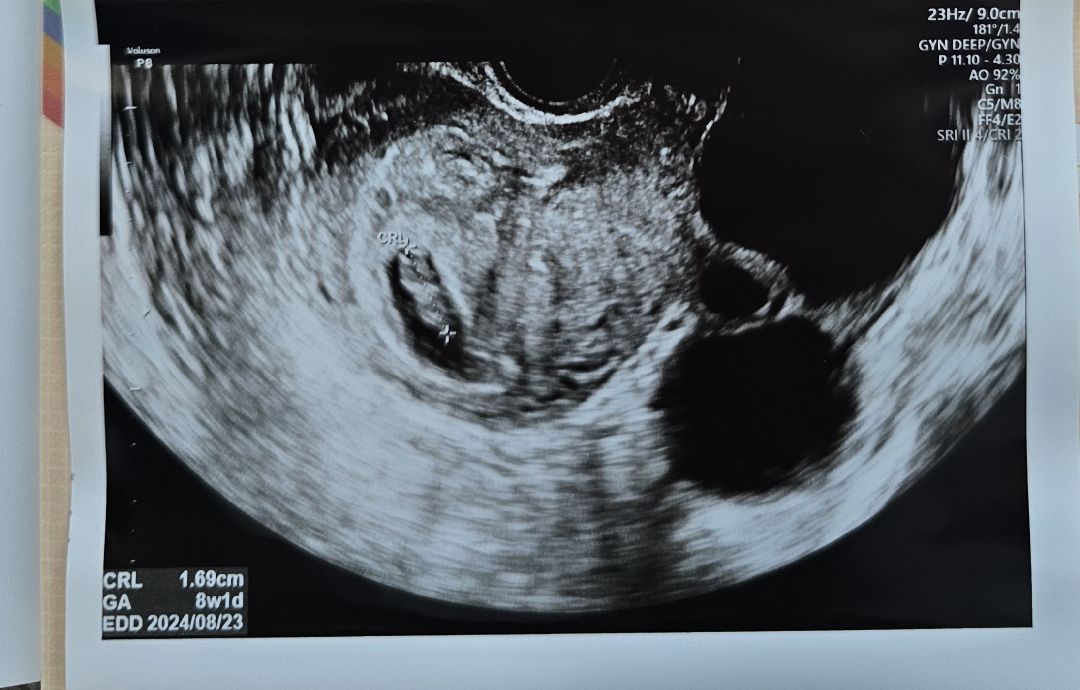

오늘 딱 8주차인데 아기보고왔는데 애기는 주수에 맞게 잘크고잇는데 그에비해 아기집이 작다네요..그전주에도 그얘기를해서 물을 2리터씩많이 마셨는데도..ㅜㅜ변화가없네요ㅜㅜ걱정이에요..애기는커가는데 집이 비좁아보여서ㅜㅜ 씬지로이드도 먹고잇엇는데 피검결과가..수치가 너무올라가서 약도 좀더 올려먹자고 하셔서 처방 받고 가는길이에요..아기집때문에 걱정이 많네요..